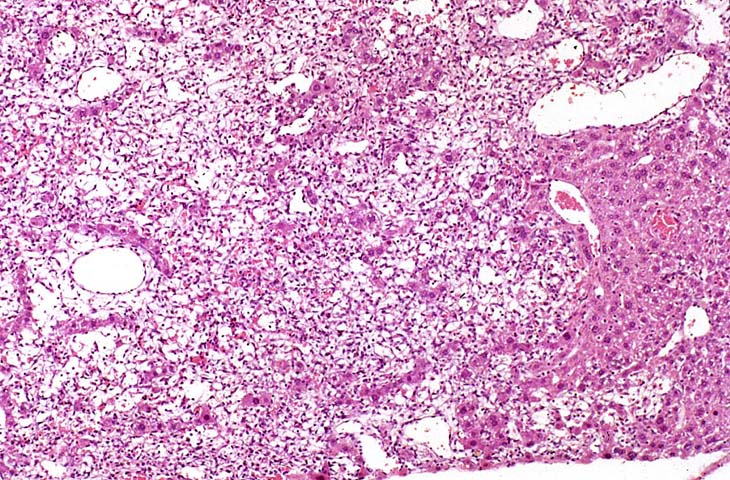

An Ito cell tumor that has replaced much of the normal hepatic parenchyma without distorting the normal contour of the liver; higher magnification shows fat-filled and stellate cells in the hepatic sinusoids.

A relative discrete Ito cell tumor is present within this hepatic lobe; a higher magnification shows proliferation of stellate cells within the hepatic sinusoidal spaces.